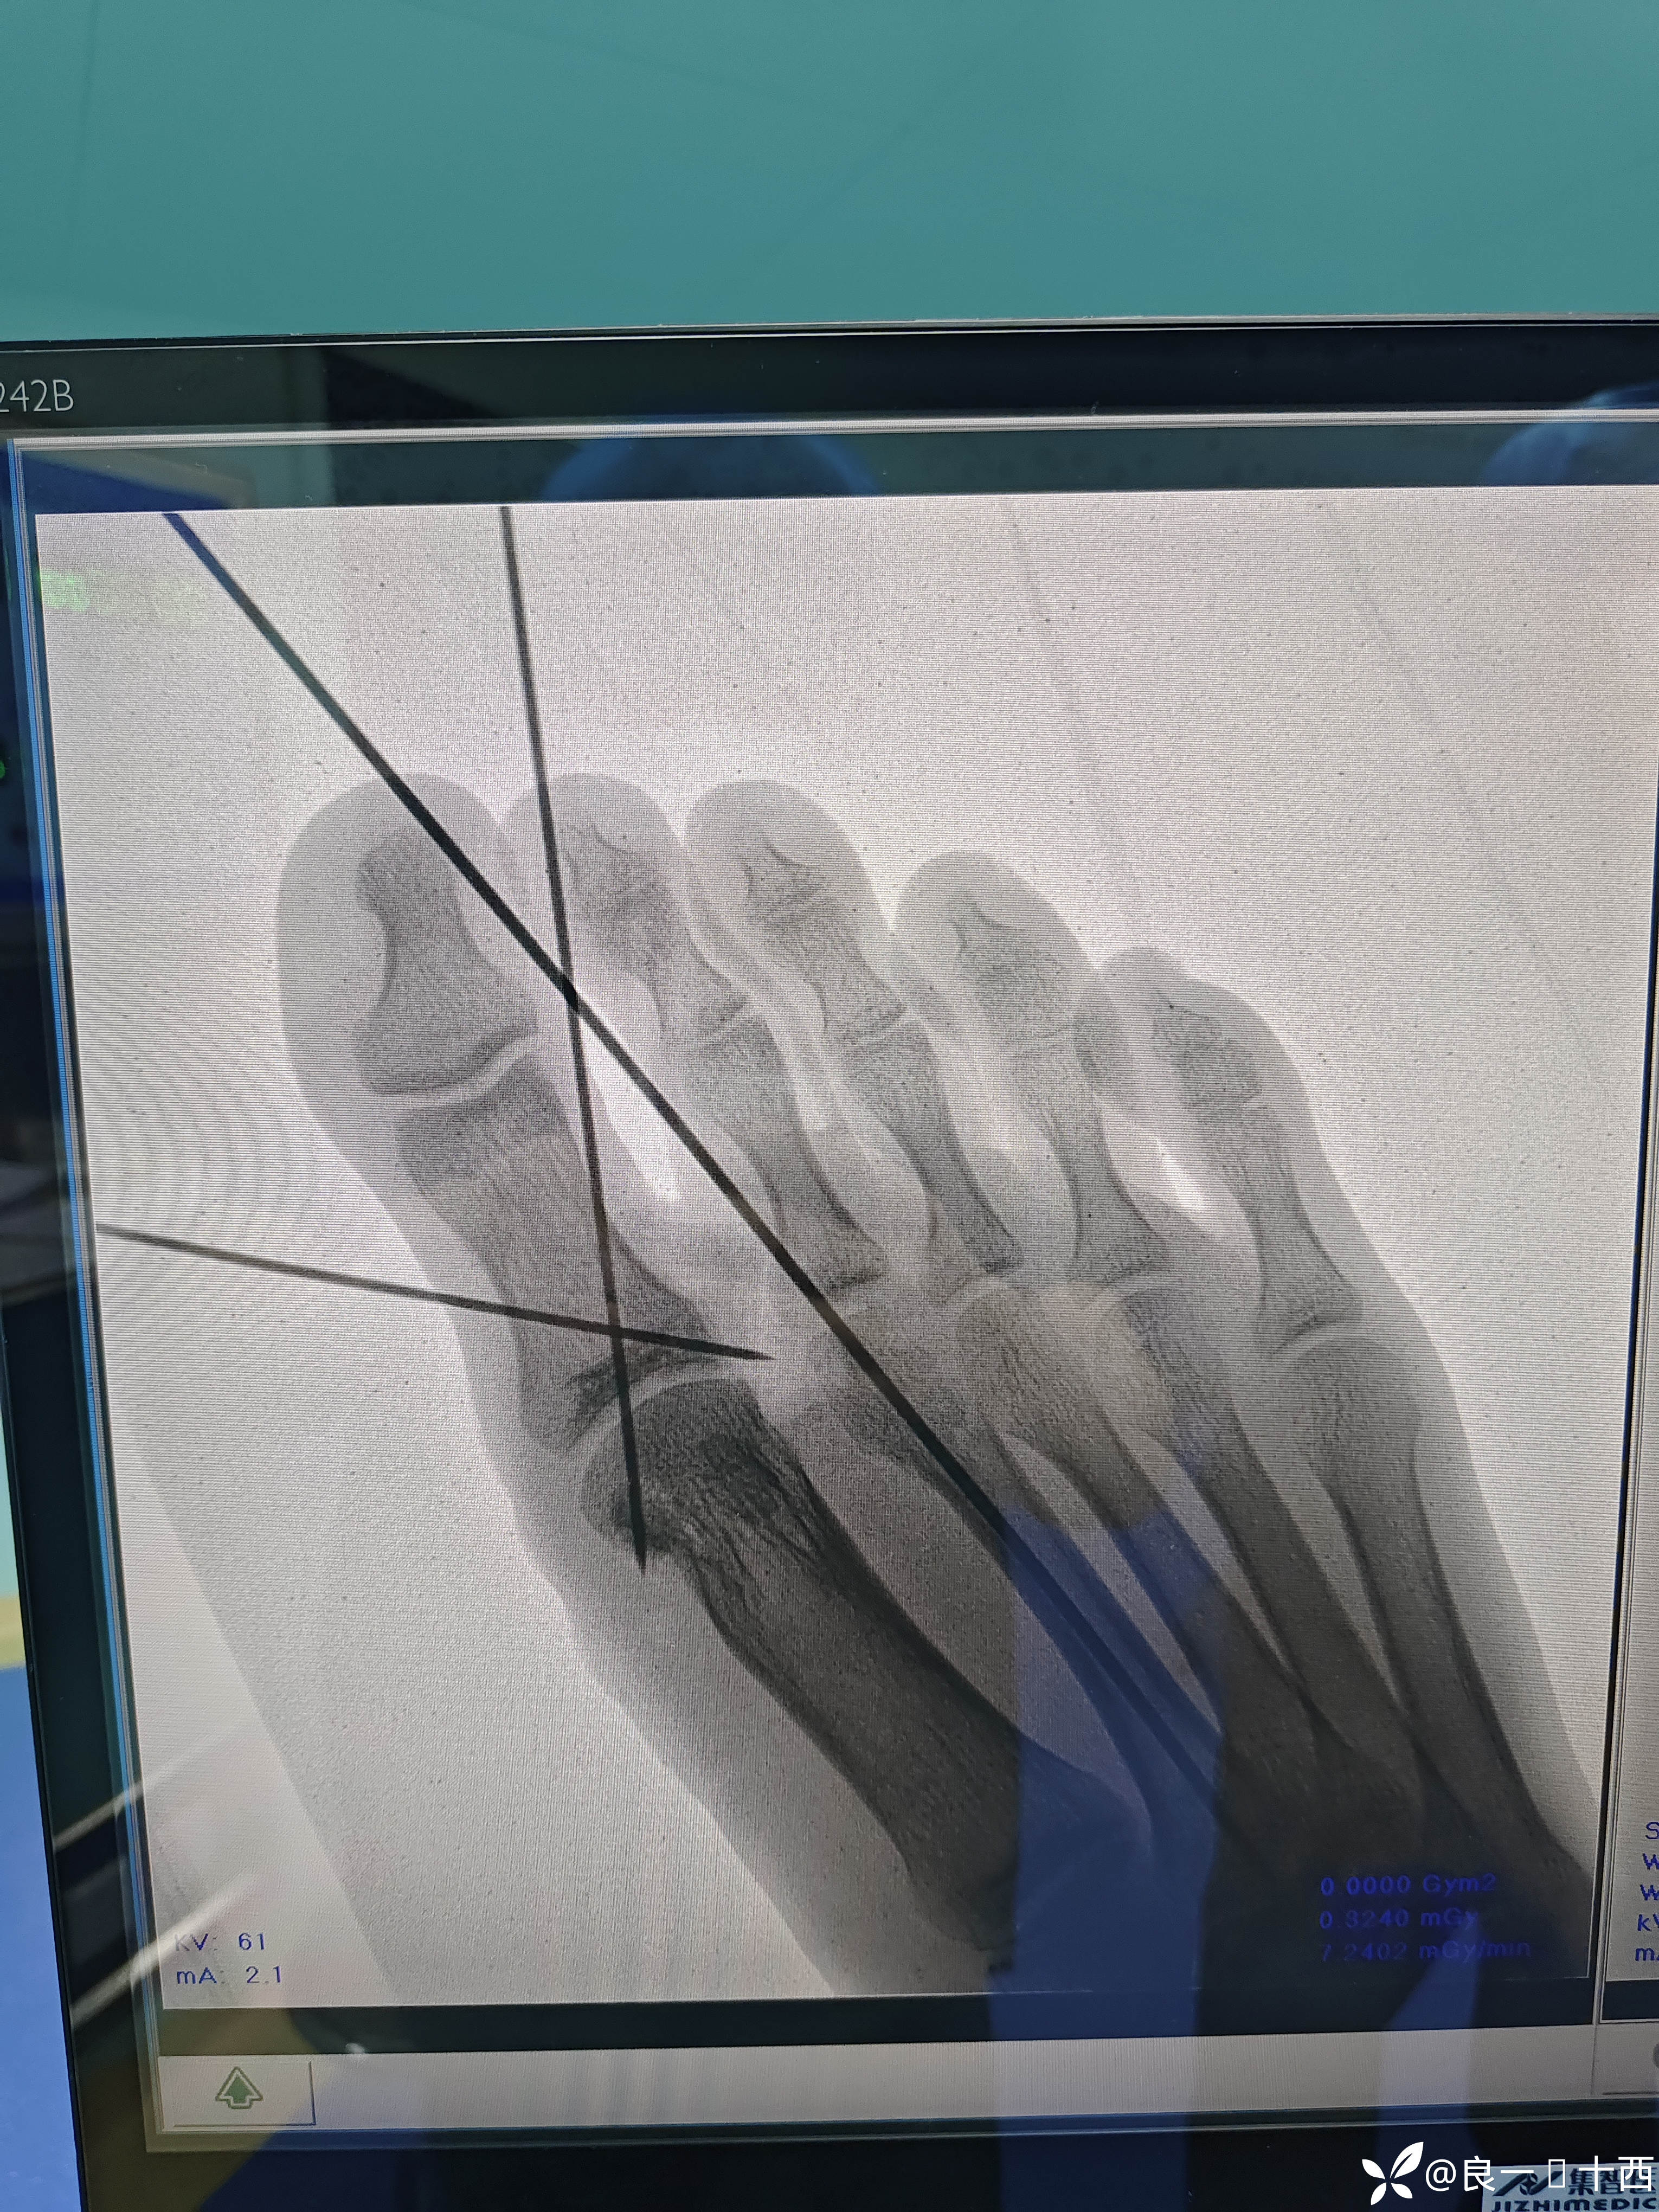

断裂的两根肌腱及位置如下图所示

术后检查,肌腱断端牢固稳定,肌腱张力合适,但是断端对位欠佳,

一开始使用的2-0肌腱线,可不知道是耐受力太差,还是我进针的距离跟张力没有调整好,连着两遍都是在改良kessler最后打结时候断裂了,前功尽弃。赶紧换了0-0的肌腱线,嗯,很结实,nice极了!使用改良kessler缝合,再使用可吸收性外科缝线,连续缝合环形加固肌腱,